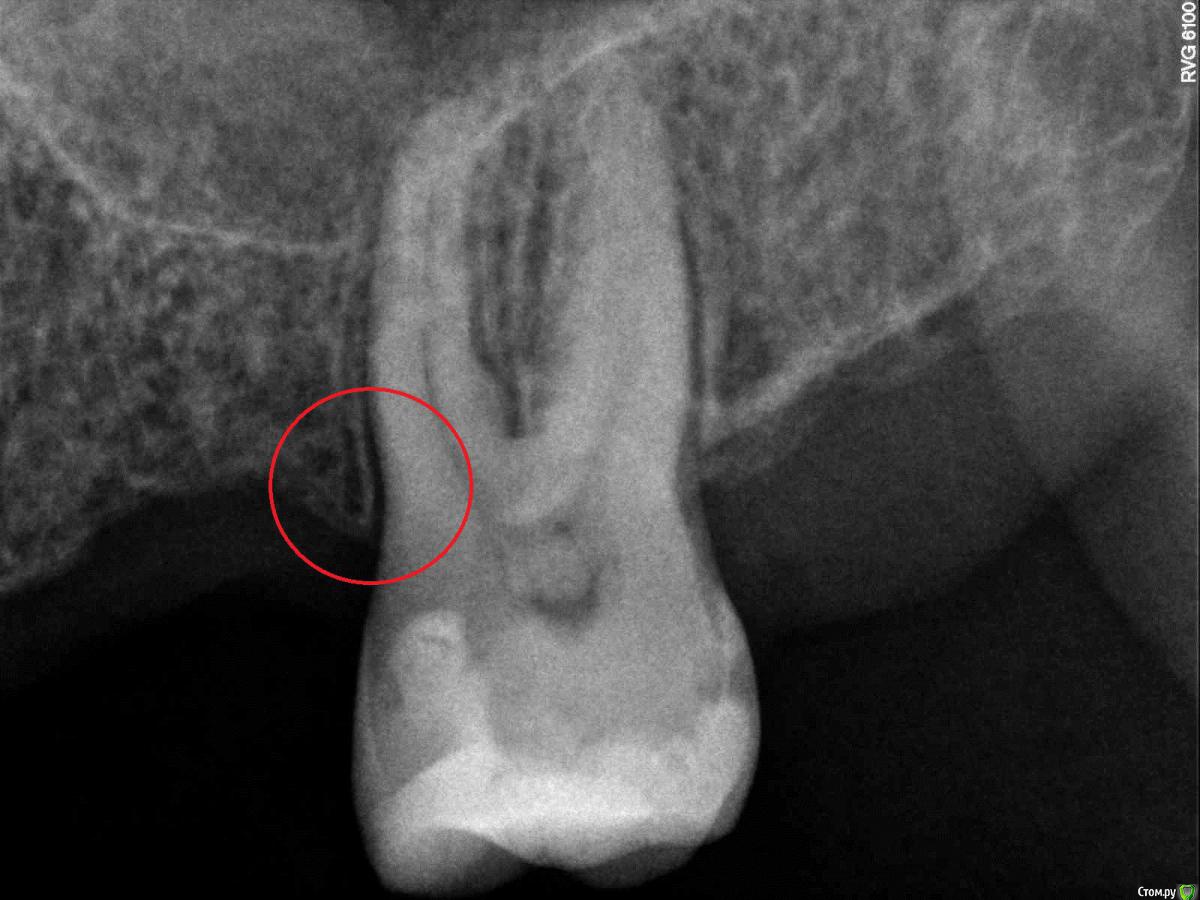

dsfksdkf Опубликовано 12 августа, 2015 Автор Поделиться Опубликовано 12 августа, 2015 (изменено) Вот в этом месте болит - черное в кости это что? С другой стороны по другому Изменено 12 августа, 2015 пользователем dsfksdkf Ссылка на комментарий

Гарриевич Опубликовано 13 августа, 2015 Поделиться Опубликовано 13 августа, 2015 То, что Вы обвели в кружок выглядит устрашающе только изза большой контрастности. Сколько это зуб стоит так одиноко? Ссылка на комментарий